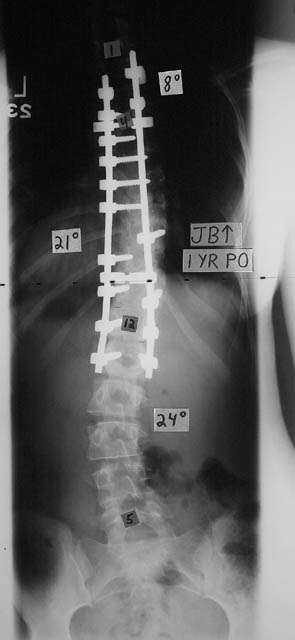

Yep, two titanium rods and a handful of screws. Can’t feel a thing and I don’t know that any of that “hardware” is there. Before surgery, I was in constant pain, had shortness of breath and wasn’t living a full life. Isn’t the difference in spinal curvature AMAZING?!

After surgery, the pain disappeared and I can do almost anything. (Except for skydiving, football, etc. Things with jarring impact on the spine.)

I had that spinal fusion in November 2000. Now, I counsel Shriners patients who are going through similar surgeries and are nervous. For more info about Str8 Spines for Shriners, just check out my Website.